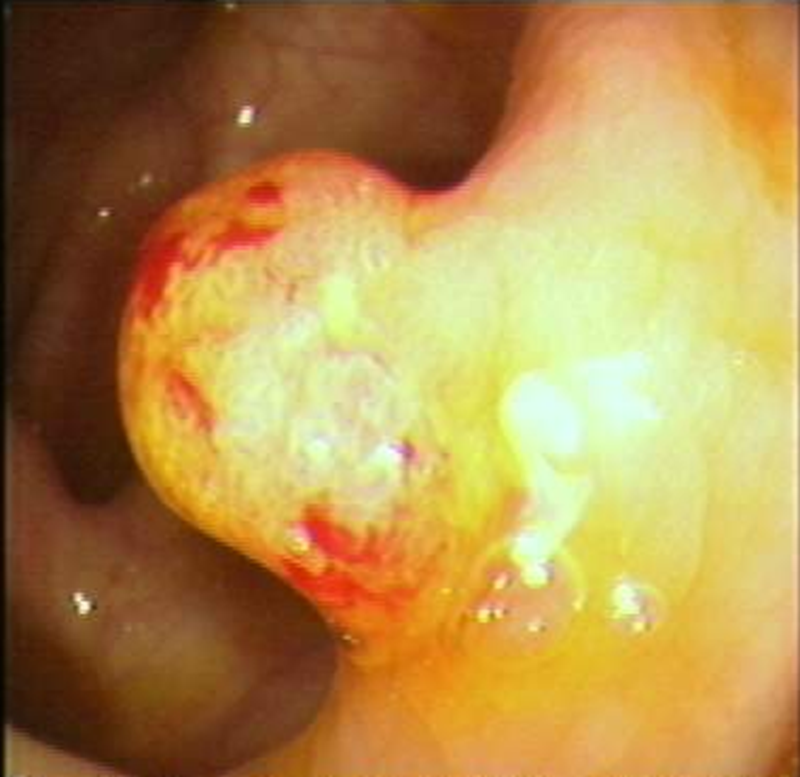

肠镜下直肠肿瘤

肠癌隆起型

直肠癌浸润型

肠癌溃疡型